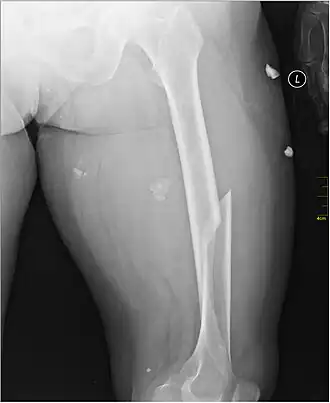

X-ray image of a femoral shaft fracture

A femoral fracture is a bone fracture that involves the femur. They are typically sustained in high-impact trauma, such as car crashes, due to the large amount of force needed to break the bone. Fractures of the diaphysis, or middle of the femur, are managed differently from those at the head, neck, and trochanter; those are conventionally called hip fractures (because they involve the hip joint region). Thus, mentions of femoral fracture in medicine usually refer implicitly to femoral fractures at the shaft or distally.